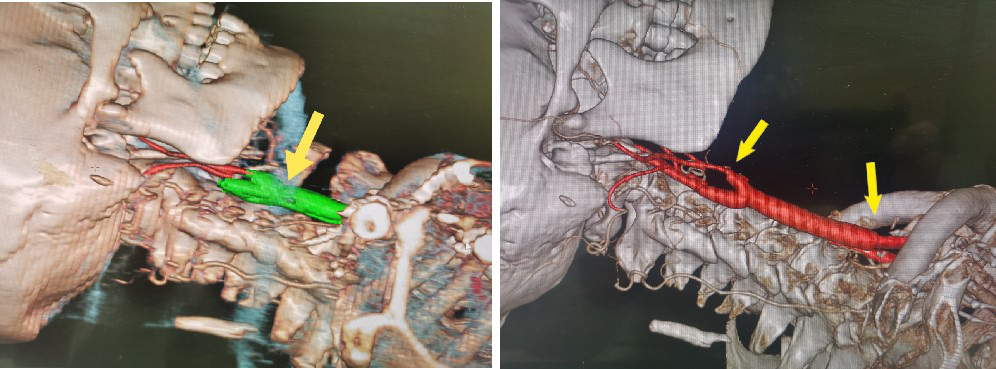

术前脑血管造影:右侧颈动脉长节段99%狭窄近闭塞(左),左侧颈内动脉起始部99%狭窄近闭塞(右)

术前CTA重建图像,绿色标记为颈动脉长节段重度钙化斑块,远端近两支颈外动脉分支显影,颈内动脉未显影(左图)

术后CTA重建图像,可见颈总动脉、颈动脉分叉及颈内动脉通畅良好(右图)

术前、术后CTA重建图像对比,可见术后右侧颈动脉严重狭窄完全解除,脑血流明显改善